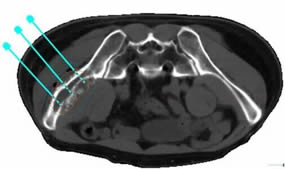

6月24日,我院介入科林征宇主任、陈锦主治医师及其团队成功开展福建省首例3D打印导向模板引导下的放射性粒子植入手术。此患者为男性,40岁,肝癌术后1年余,发现左髂骨转癌半年,行外放疗+索拉非尼靶向治疗后肿瘤残留,症状表现为左髋部疼痛,站立及行走时明显,影响日常生活及睡眠。根据患者术前的CT图像,医疗团队在PROWESS TPS软件中确定肿瘤的大小、位置及与危及器官的毗邻关系,利用计算机模拟设计一个与体表完全吻合的模板,并在模板上设计出植入粒子的“针道”,按照瘤体照射剂量的TPS计划设计每个“针道”的深度、角度及植入粒子的数目,精心的术前准备使得术后结果与术前计划高度吻合,做到了更加便捷、精准、微创,使瘤体局部放射学剂量最优化。

术前设计进针路线和粒子规划